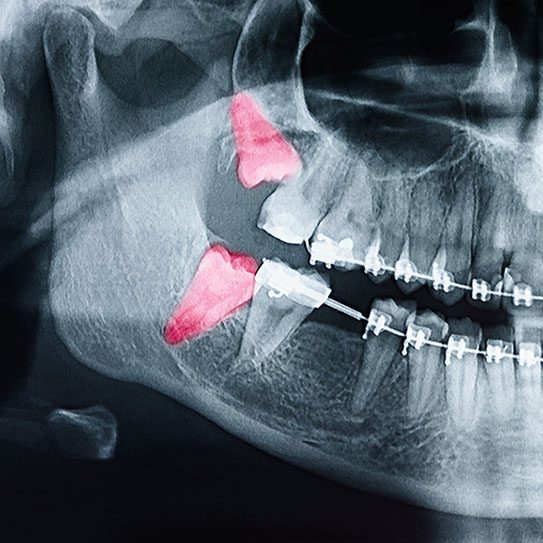

Wisdom teeth are located at the very back of the mouth. Many people do not have enough room in their jaws for these teeth to come in properly. When space is limited, wisdom teeth may become impacted, partially erupt through the gums, or grow at an angle. These issues can cause pain, swelling, and even infection.

Orthodontists and general dentists use X-rays to monitor the position and development of wisdom teeth. If your dental team sees signs that your wisdom teeth could cause problems, such as impaction or crowding, they may suggest removing them.